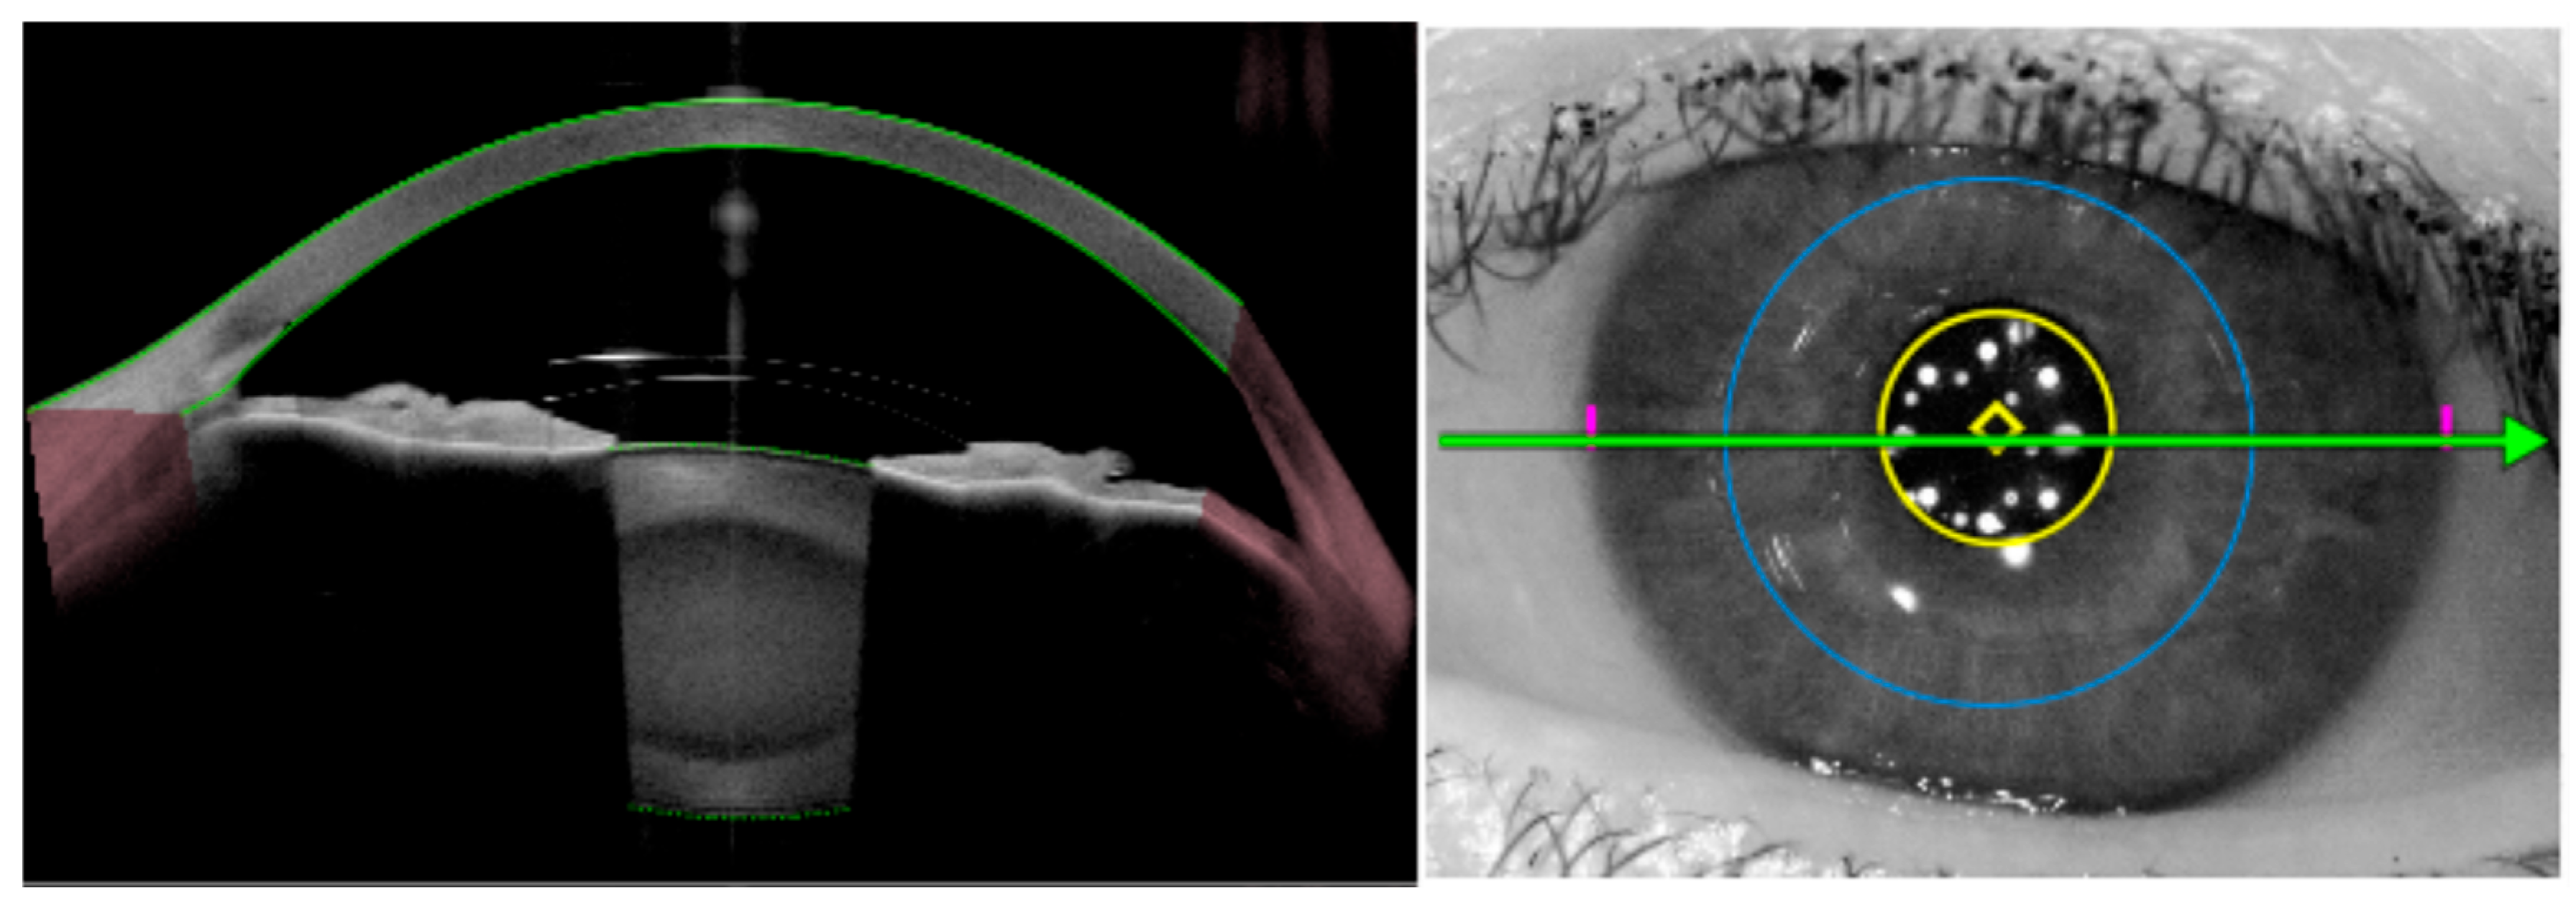

One of the foremost uses of anterior segment OCT is to measure the central vault of posterior chamber pIOLs like the ICL (Figure 1). The vault is defined as the perpendicular distance between the posterior pIOL surface and the anterior crystalline lens capsule. A widely cited target considered ideal is a vault of approximately 250–750 μm in normal lighting conditions. In a properly sized ICL, the vault remains sufficient even under physiological changes [17,18,26,27]. Normative vault ranges have been established in large studies using OCT and reporting an average vault of around 500–600 μm with standard deviations of ~200 μm [28,29,30,31].

Postoperative vault is critical to minimize complications. Approximately 5–10% of eyes may end up with low (<250 μm) or high (>1000 μm) vaults even with formula-based sizing [14]. OCT can detect scenarios like an oversized ICL causing iris convexity (iris pushed forward by a high vault) or an undersized ICL that is “collapsing” onto the crystalline lens. It is indispensable to identify these outliers early so that prophylactic measures can be taken (e.g., prophylactic iridotomy for a high vault to prevent block, or ICL exchange for a very low vault to prevent cataract) [17].

If the vault is too low, for example, due to a severely undersized or dislocated ICL, it may come into direct contact with the crystalline lens—something that can precipitate an anterior subcapsular cataract often before it is visible clinically [32]. OCT might reveal focal obliteration of the space between ICL and crystalline lens, or a hyperreflective change on the anterior crystalline lens capsule suggestive of early cataractous change [33]. In extreme cases, an OCT scan may directly show lens contact. In extreme cases, long-term ICL–crystalline lens contact can occur, leading to cataract formation; such complications have been documented in clinical series, where OCT findings and clinical progression prompted ICL explantation [32]. On the other hand, if the vault is excessive, it can crowd the anterior chamber, elevating intraocular pressure or causing angle closure or iris pigment dispersion, as well as alterations in pupillary dynamics that could lead to focusing difficulties and halos [34,35].

2.3.4. Angle Anatomy

Fourier-domain and swept-source anterior segment OCT can image the iridocorneal angle in detail. After pIOL implantation, angle anatomy often changes: posterior chamber ICLs typically cause a mild reduction in angle width and volume because the iris is slightly pushed forward by the ICL (Figure 2). A study revealed postoperative angle opening distance decreased by ~20–25% after ICL, though the angles generally remained open in appropriately selected eyes [27]. Similarly, our group determined iridocorneal angle changes prospectively in ICL patients, indicating initial angle narrowing of 39–45% which was stable beyond 1 month postoperative [39].

On the other hand, anterior chamber pIOLs (angle-supported lenses) can cause even more pronounced angle shallowing and sometimes focal synechiae formation at the lens footplates, which can be visualized with anterior segment OCT [40,41].

Pupillary block glaucoma is a pIOL-related emergency that occurs when aqueous flow from posterior to anterior chamber is impeded, causing iris bombe (forward bowing of the iris) and acute angle closure. In pIOL patients, this can happen if the PI is blocked, if an ICL without a central port traps fluid or if pigment or viscoelastic obstructs the central port [42,43].

Clinicians have reported using OCT to differentiate pupillary block from other causes of high intraocular pressure. In pupillary block, the OCT shows the iris bowed forward in a classic “iris bombe” convexity contacting the lens or ICL, with a deep posterior chamber and shallow anterior chamber. Anterior segment OCT can confirm iris bombe configuration, even when a hazy cornea or a small pupil limits the gonioscopic view [44]. Anterior segment OCT allows for a precise evaluation of hyperopic ICL cases, which usually present with narrower baseline angles, as well as for monitoring the dynamic changes in vault and angle configuration that occur with miosis and mydriasis (Figure 3 and Figure 4).

Figure 1. Vault assessment and angle configuration in phakic IOLs. (A,B) Preoperative anterior segment optical coherence tomography (AS-OCT) and optimal vault (~500 µm) after implantable Collamer lens (ICL) implantation, respectively; (C,D) Preoperative AS-OCT and high vault (>1000 µm) after ICL implantation, respectively; (E,F) Preoperative AS-OCT and low vault after ICL implantation (<250 µm), respectively.